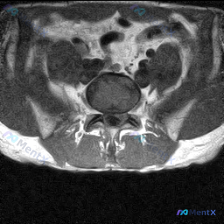

看到一个挺有警示意义的读片场景,整理出来和大家分享一下。 基本临床场景 临床怀疑患者存在椎间盘病变,提供了一张T2加权冠状位磁共振影像,请读片判断是否存在椎间盘病变,拿到的影像分析结果如下: 现有影像分析内容: 1. 双侧肾脏轮廓清晰,位置大小正常,肾周脂肪间隙清晰,无渗出模糊影 2. 肾脏皮髓质分...

看到这个读片需求,整理了完整的分析思路分享给大家。 病例基础信息 用户提供一张腹部MRI轴位T2加权图像,问题是:判断这张影像上是否存在椎间盘病变。 第一步:影像基础评估 先给大家整理这份影像的客观发现: 1. 图像质量:对比度良好,能清晰显示腹膜后结构,无明显运动伪影 2. 解剖定位:这是上腹部/...